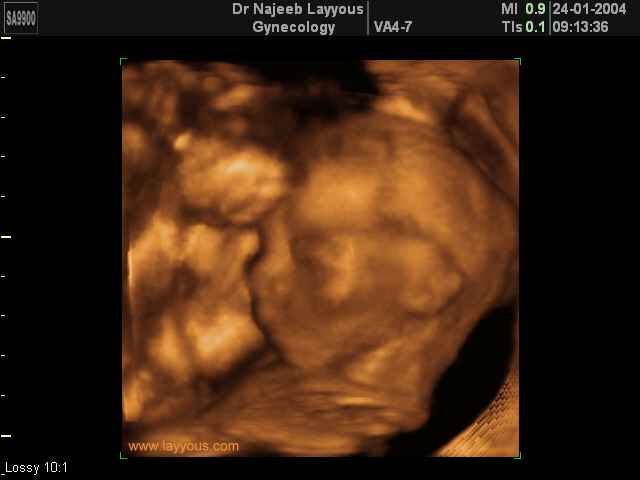

3D second trimestre échographie Photos de numérisation - deuxième partie de la grossesse | Dr N Layyous

3D second trimestre échographie Photos de numérisation - deuxième partie de la grossesse